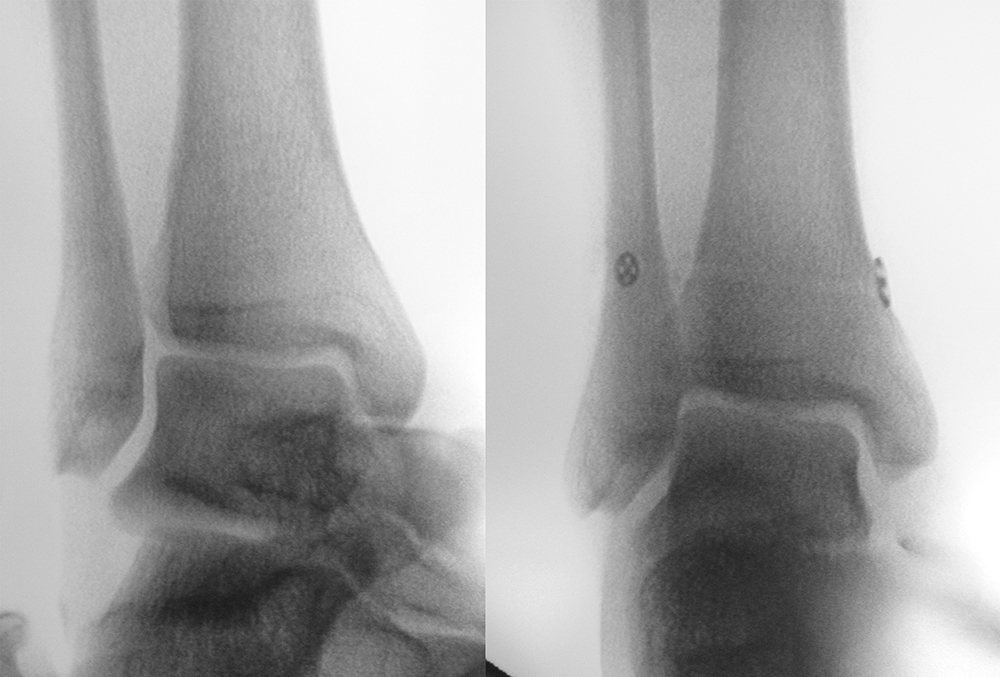

Die eigentliche Reposition der Syndesmose erfolgt mittels einer Repositionszange über dem Malleolus medialis und lateralis, entlang der Achse des oberen Sprunggelenkes und wird nach Reposition in anatomischer Stellung fixiert 52. Dabei ist auf eine Neutralstellung im oberen Sprunggelenk zu achten. Die temporäre Fixierung des DTFG kann mittels Schraube(n) oder einem dynamischen System (Suture Button - z.B. Tight-Rope, Fa. Arthrex™) erfolgen. Bei der Fixierung mittels Schraube können eine oder zwei Schrauben von 3,5-4,5 mm Stärke, tri- oder quadricortical, verwendet werden 53. Dies werden am posterolateralen Rand der Fibula in leicht aufsteigender Technik (30°), circa 2 cm und 3,5 cm oberhalb der tibiotalaren Gelenkfläche, parallel zur OSG-Achse nach entsprechendem Vorbohren eingebracht. Eine Schraubenpositionierung 2 cm oberhalb der tibiotalaren Gelenkfläche konnte in biomechanischen Untersuchungen eine bessere biomechanische Stabilität des DTFG gewährleisten als eine Positionierung der Schraube weiter proximal 54. Keinen Vorteil gegenüber tricortical eingebrachten Stellschrauben wiesen dagegen Schrauben auf, welche vier Corticalices fassen 55. Ob eine Entfernung der Syndesmosenstellschraube sinnvoll ist oder nicht, ist bist heute Bestandteil der internationalen Diskussion 56. Wir Entfernen Stellschrauben nach ca. 6 Wochen bei erhaltenem PITFL, sind alle Syndesmosenbänder verletzt, wird die Stellschraube 8 Wochen belassen.

Alternativ können verschiedene dynamische Systeme verwendet werden. Hierbei erfolgt, wie oben beschrieben, die Reposition der DTFG mittels Repositionszange. Anschließend wird in derselben Technik, wie bei der Syndesmosenstellschraube, quadricortical vorgebohrt. Hierauf wird durch den vorgebohrten Tunnel das Fadensystem (Suture-Button) von lateral nach medial durchgezogen und medial transkutan über die an dem Fadenende befestigte Nadel ausgeleitet. Über das speziell angebrachte Fadensystem lässt sich der mediale Button parallel zur medialen Kortikalis ausrichten und durch Zug am lateralen Faden an die medialen Tibiakortikalis heranzuiehen. Anschließend wird durch Anspannen der lateralen Fadenenden der laterale Button auf der Fibula platziert. Nach Erreichen der gewünschten Festigkeit und Reposition des DTFG werden die lateralen Fadenenden verknotet und abgeschnitten. Die medialen Fadenenden werden ebenfalls entfernt. Ziel des dynamischen Stabilisierungsverfahren ist eine physiologische Bewegung im DTFG zu ermöglichen bei gleichzeitiger Sicherung der Gelenkstabilität 57. Eine Materialentfernung ist bei diesen Systemen nicht zwingend erforderlich. Bei der ersten Generation der Suture-Button-Systeme sind Hautirritationen und Wundheilungsstörungen in ca. 10% der Fälle beschrieben. Ob diese durch die inzwischen erhältlichen knotenlosen Systeme vollständig verhindert werden, ist Gegenstand aktueller Untersuchungen.